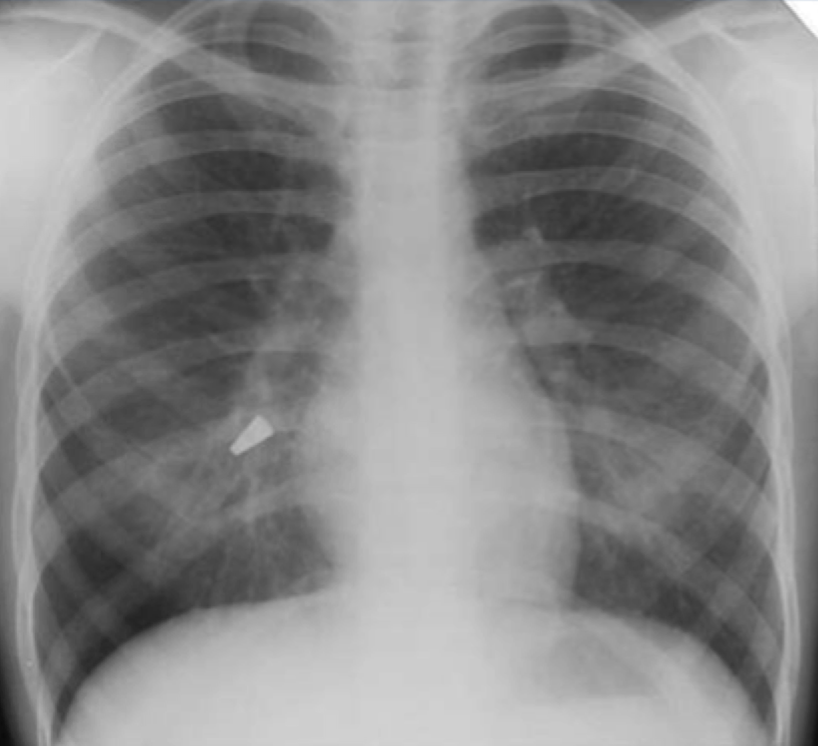

12

Q

?

A

acute respiratory distress syndrome

- normal heart

-no pleural effusion

-bilateral widespread pulmoonary inflitrates

-air bronchograms